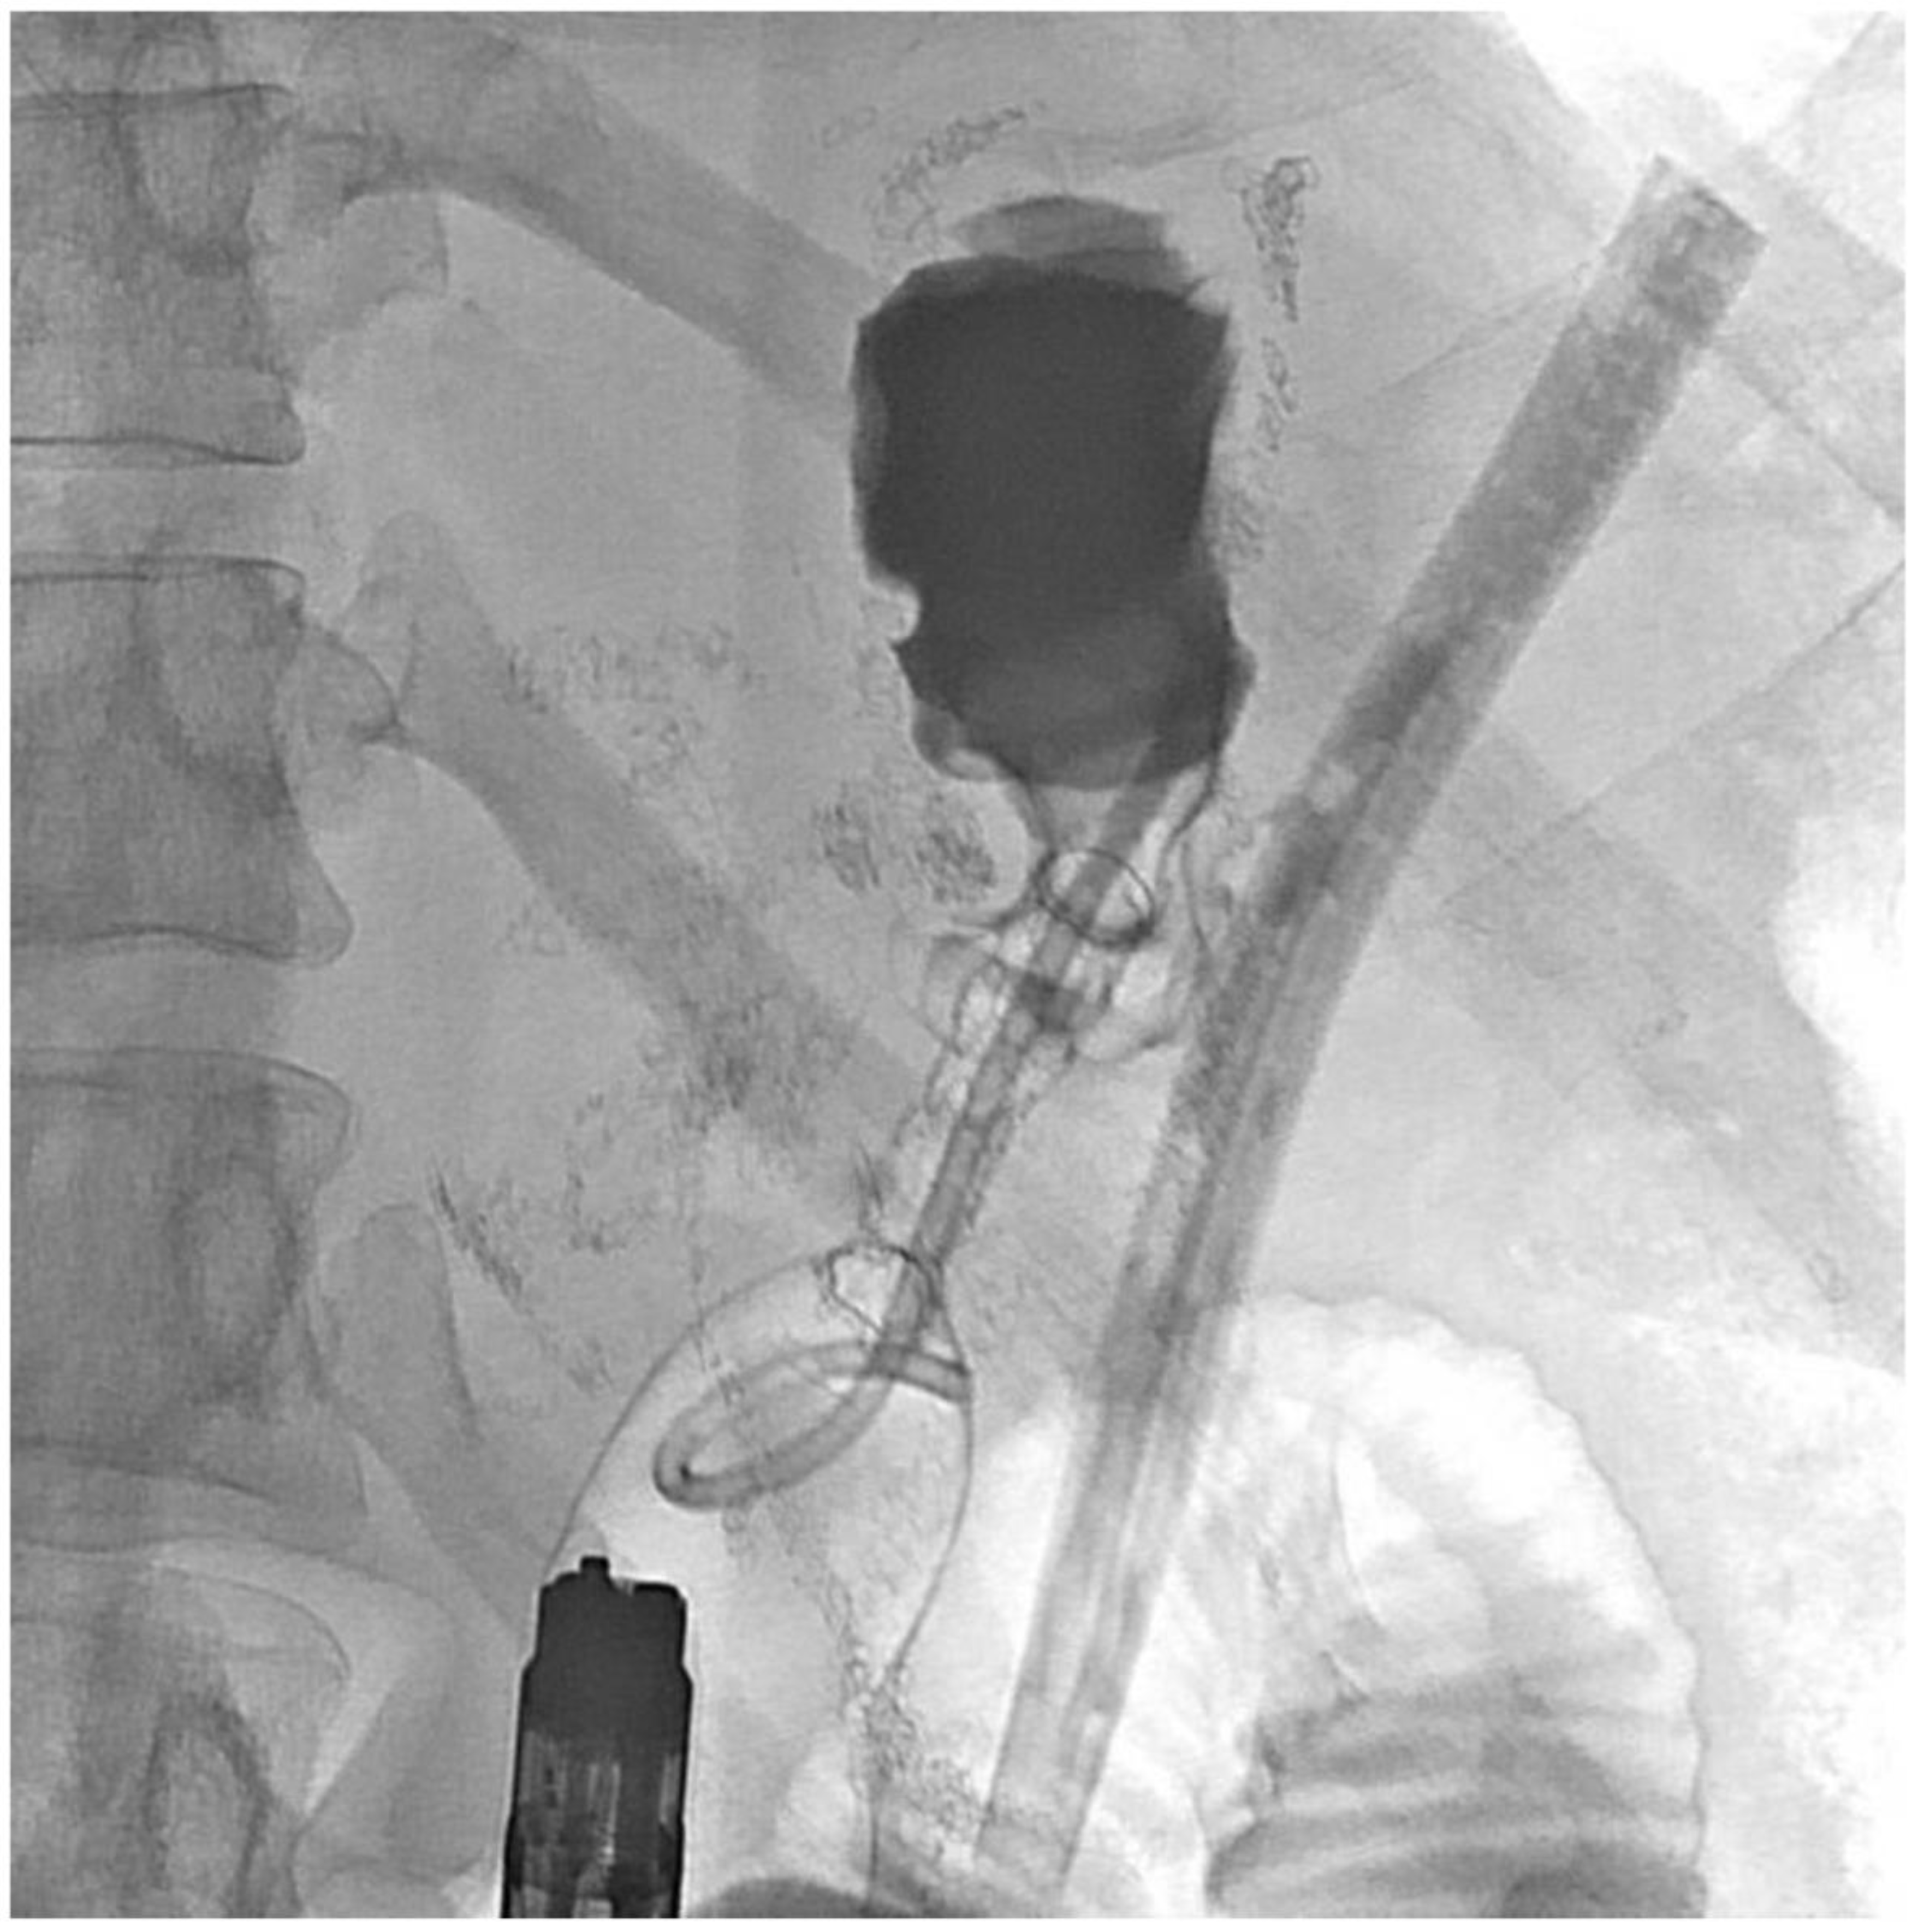

2. Detailed Case Description